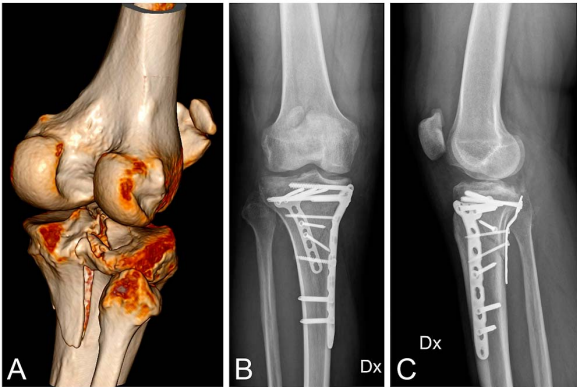

剥离后,在胫骨平台 L 形区域内可视化后外侧骨块并清除软组织。图 3 显示了通过内侧入路和后外侧 (Frosch) 入路进行内侧和后侧钢板固定的临床病例。

图 3 一名受右胫骨平台后外侧骨折影响的 42 岁男性患者的术前 CT 扫描 (A)。6 个月时的前后位 (B) 和侧位 (C) X 光片显示通过 Frosch 入路和内侧入路进行的后路人工骨植骨和支撑钢板固定加内侧钢板固定,具有优异的影像学结果。